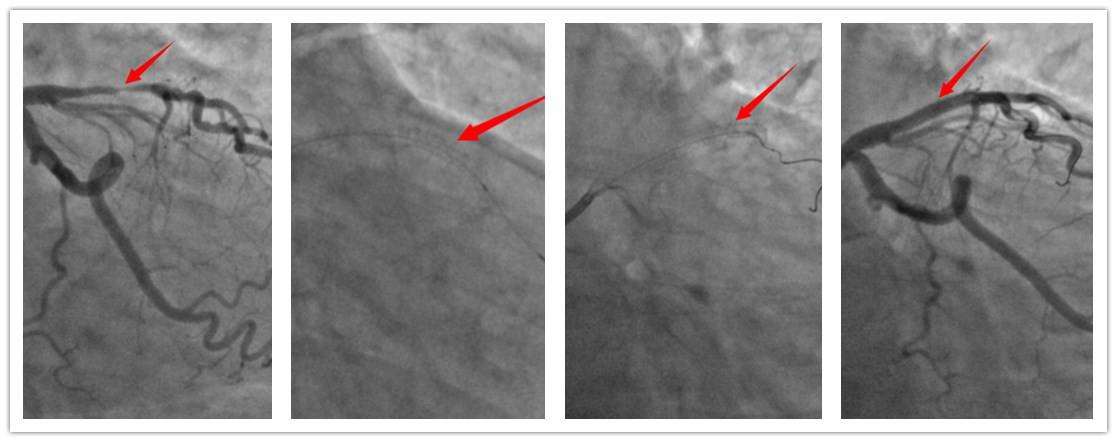

据了解:多层螺旋CT心脏和冠状动脉成像是一项无创、低危、快速的检查方法,CT冠状动脉造影CTA(CT coronary angiography CTA),是近几年才出现的新技术,已逐渐成为一种重要的冠心病早期筛查和随访手段。这种方法是从手臂的静脉里输入对比剂,就象平时输液是一样的道理,因其几乎没有创伤性,非常安全,因不用插管,所用时间也短。对冠脉病变的阴性率为98%,阳性率为90%。适用于:①不典型胸痛症状的患者,心电图、运动负荷试验或核素心肌灌注等辅助检查不能确诊。②冠心病低风险患者的诊断。③可疑冠心病,但不能进行冠状动脉造影。④无症状的高危冠心病患者的筛查。⑤已知冠心病或介入及手术治疗后的随访。

开发区第一人民医院提醒大家:冠心病的发作常常与季节变化、情绪激动、体力活动增加、饱食、大量吸烟和饮酒等有关。典型症状为胸痛,因体力活动、情绪激动等诱发,突感心前区疼痛,多为发作性绞痛或压榨痛,也可为憋闷感。如有上述不适,请到正规医院检查,以及早确诊及时治疗保障生命安全。